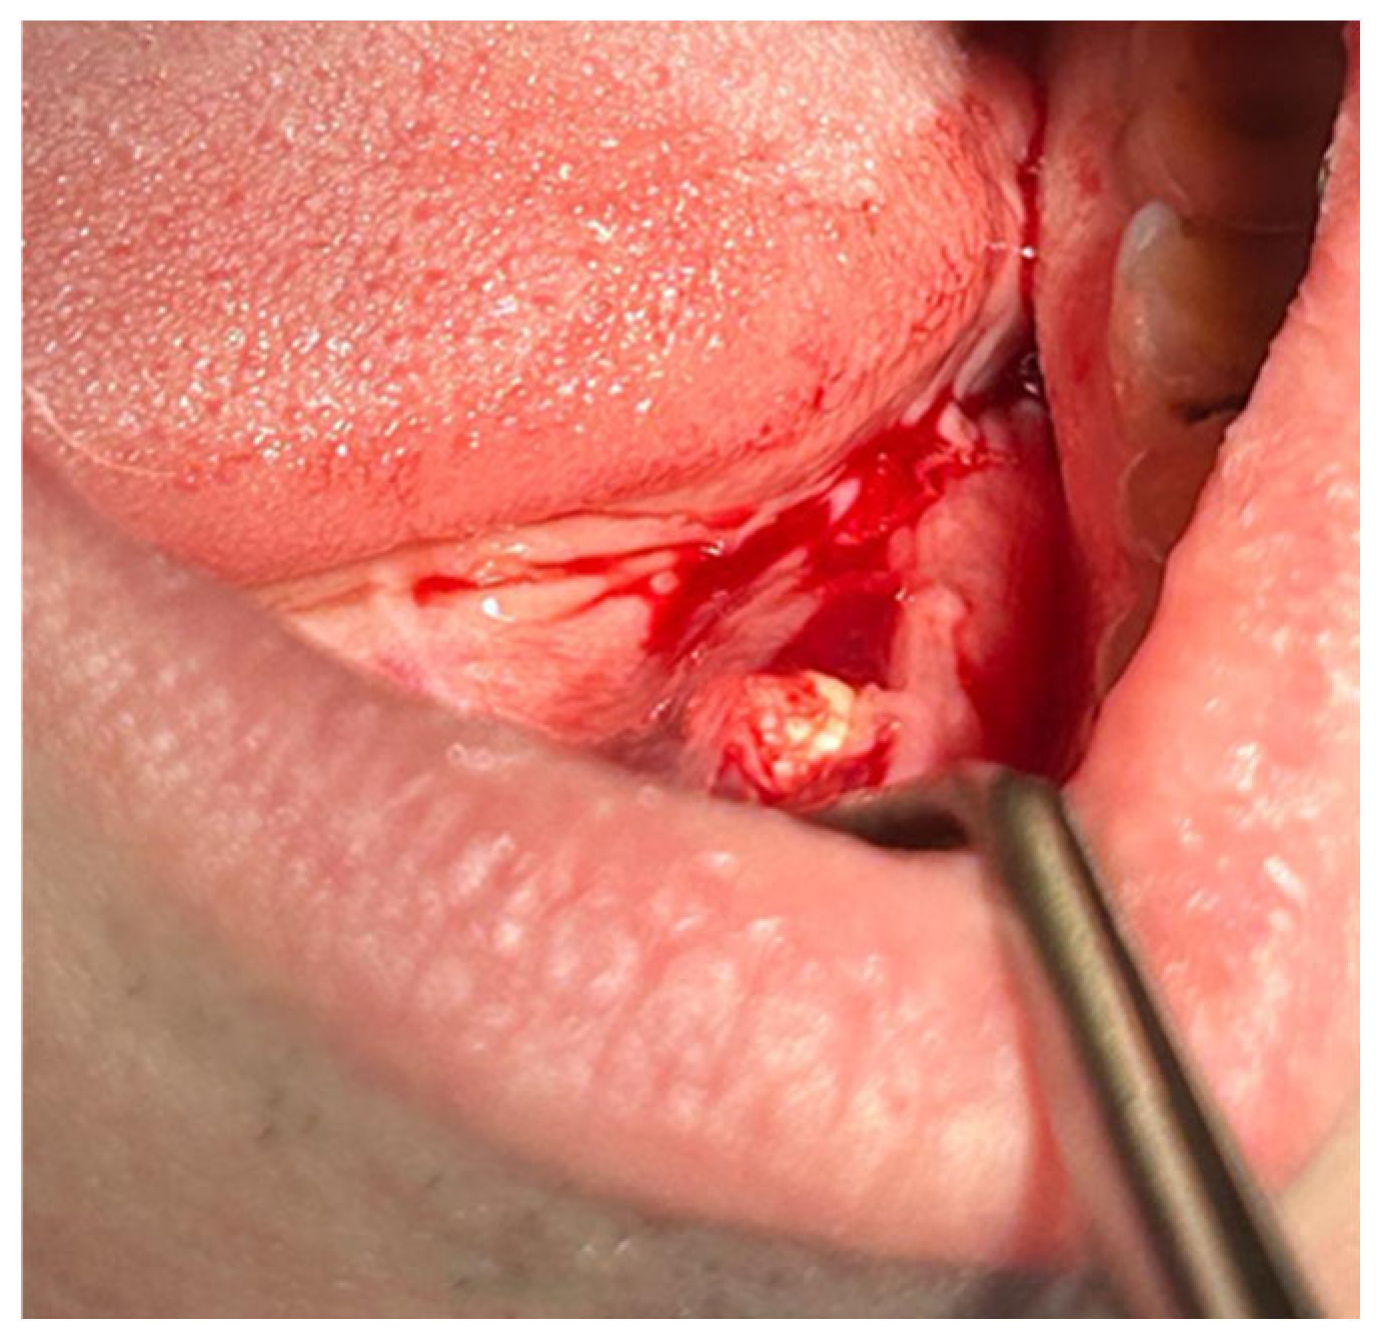

4.1. Clinical Case